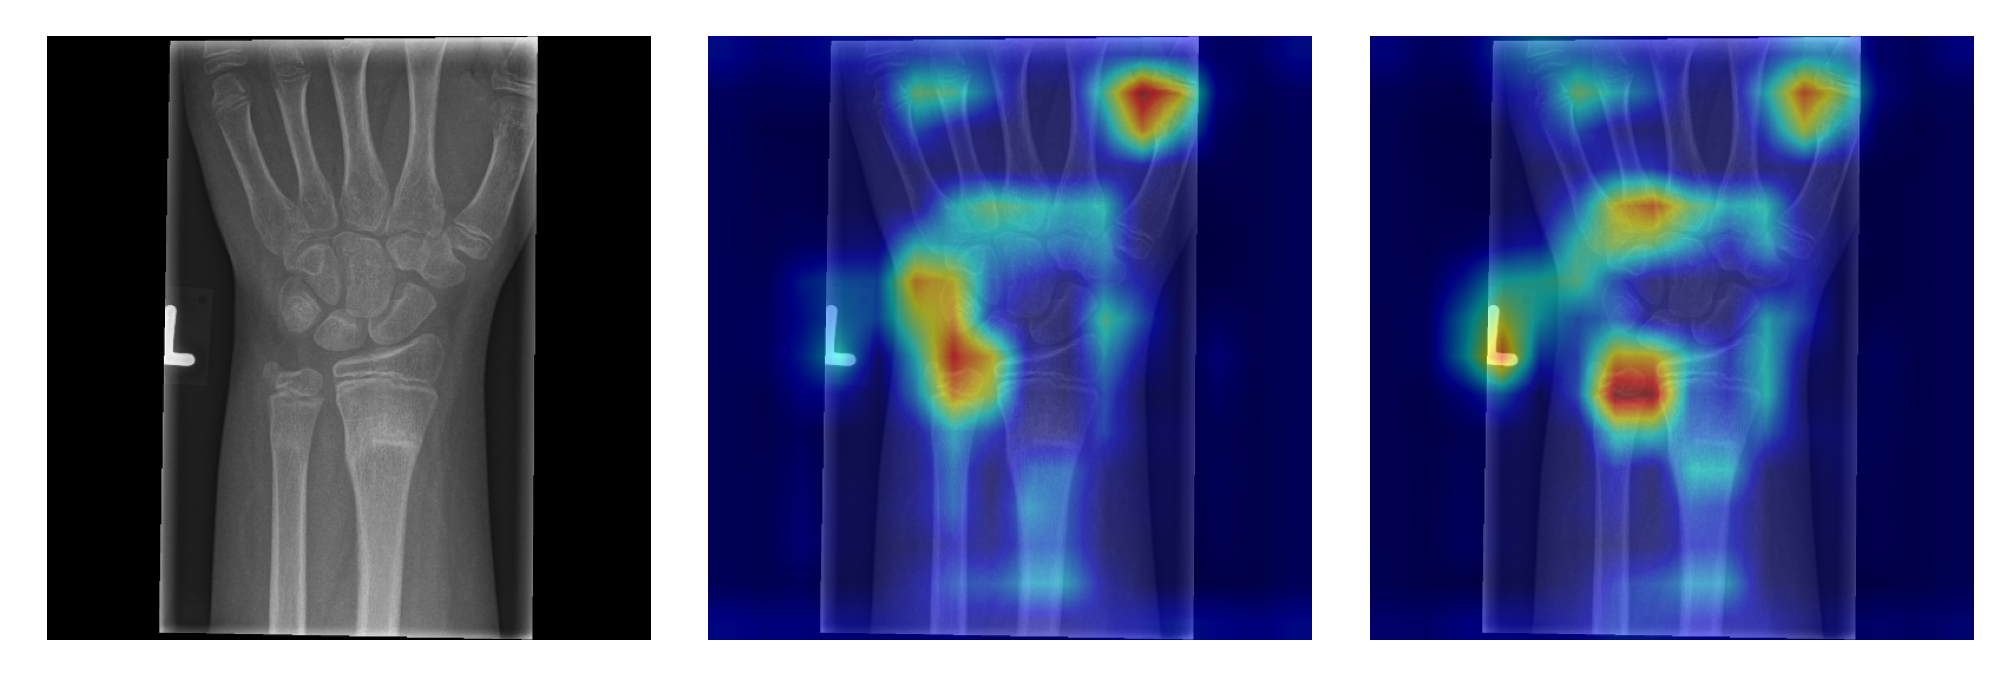

This is project about CNN using for classification of osteoporosis, osteopenia pathologies and normal structure of bones